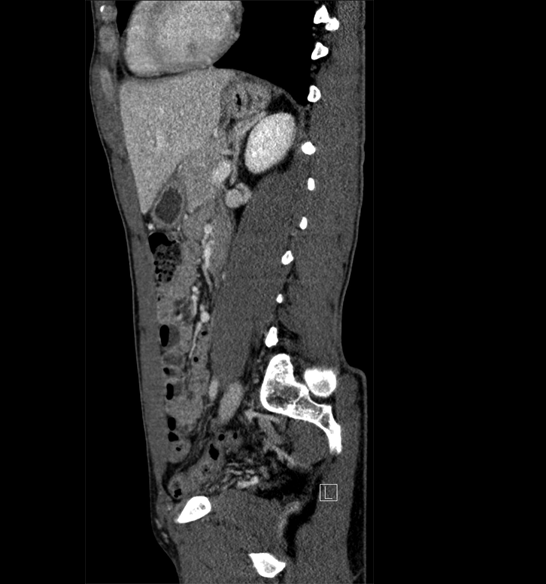

Body

Covers abdominal CT anatomy.